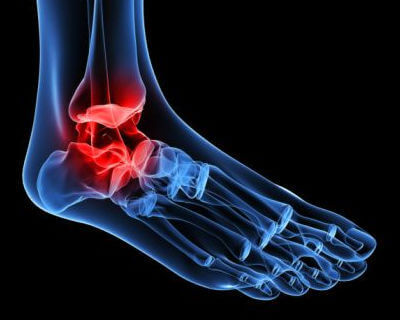

Ayak bileği kireçlenmesi birçok insanın yaşam kalitesini sınırlar. Hareketliliği engelleyen, sessiz ve kalıcı bir hastalıktır. Dahası, yol açtığı ağrı, ilaç aldıktan sonra bile azalmayabilir.

Her geçen gün daha fazla kişi kalça ya da diz aşınması ve yıpranması gibi kemik problemleriyle karşılaşıyor. İşte bu problemlerden biri olan ayak bileği kireçlenmesi, dejeneratif hastalıklarla bağlantılı olan osteoartritin çok yaygın bir türüdür.

Ayak bileği eklemlerinin yürümek için çok önemli olduğunu unutmamalıyız. Buna ek olarak, kalça, diz ve ayağın oluşturduğu postural eksenimizin uyum içinde olması adına, ayak bileğinin sahip olduğu fonksiyon vazgeçilmezdir.

Bu tip bir artroz, ayak bileği eklemindeki kıkırdağın aşamalı olarak aşınması ve yırtılmasından kaynaklanır. Yaşlandıkça ayak bileklerinde sertleşme ve deformasyon oluşması yaygın bir durumdur.